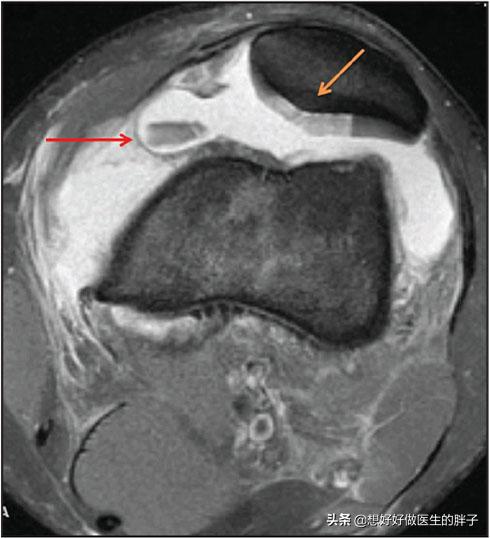

大家一定要知道,在髌骨的后方有非常重要的一层软骨结构,这种结构可以起到非常重要的缓冲髌骨承受的压力,增加关节腔的润滑的作用,这层结构我们称之为髌骨后方的关节软骨。当膝关节受到迎面而来的*力暴**伤害时,这人有时候并不能导致髌骨发生骨折,有可能会造成髌骨的内部骨挫伤,也有可能在*力暴**伤害的过程当中导致髌骨后方的软骨发生碎裂脱落,这种情况其实并不少见。

大家看下图的核磁影像当中,红色箭头所指的部位就是受外伤以后掉落下来的关节软骨,而黄色箭头所指的是这块软骨原来所附着的位置,另外一张图是是髌骨碎裂以后术中的影像资料。

红色箭头所指为脱落软骨碎块

髌骨软骨缺损